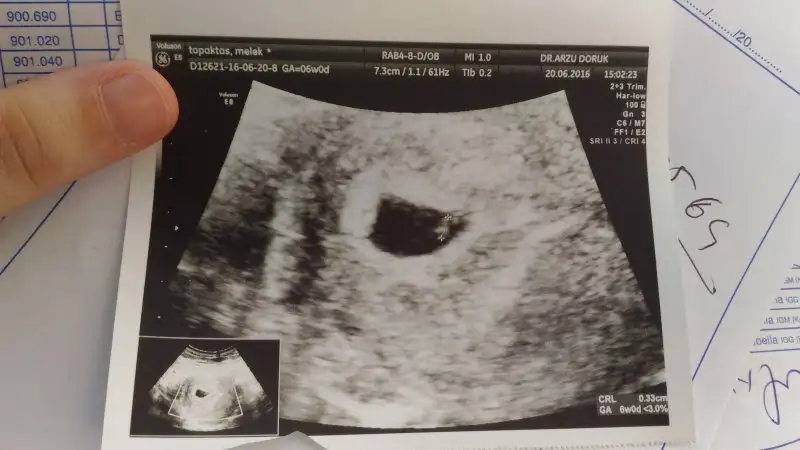

tedaviyle olunca genelde çoğul gebelik oluyor zaten haydi bakalım gözün aydın şimdidenAy benim değerim 1202 'ydi dr tahmini çıkacak mi acaba. Randevuya 10 gün var daha. Bakalım hakkımızda hayırlısı. Ben tedaviyle olduğu için bir iki üç hepsi olabilir razıyım. olmayınca çok uğraştım. Rabbim sağlıkla kucağına almayı nasip etsin![]()